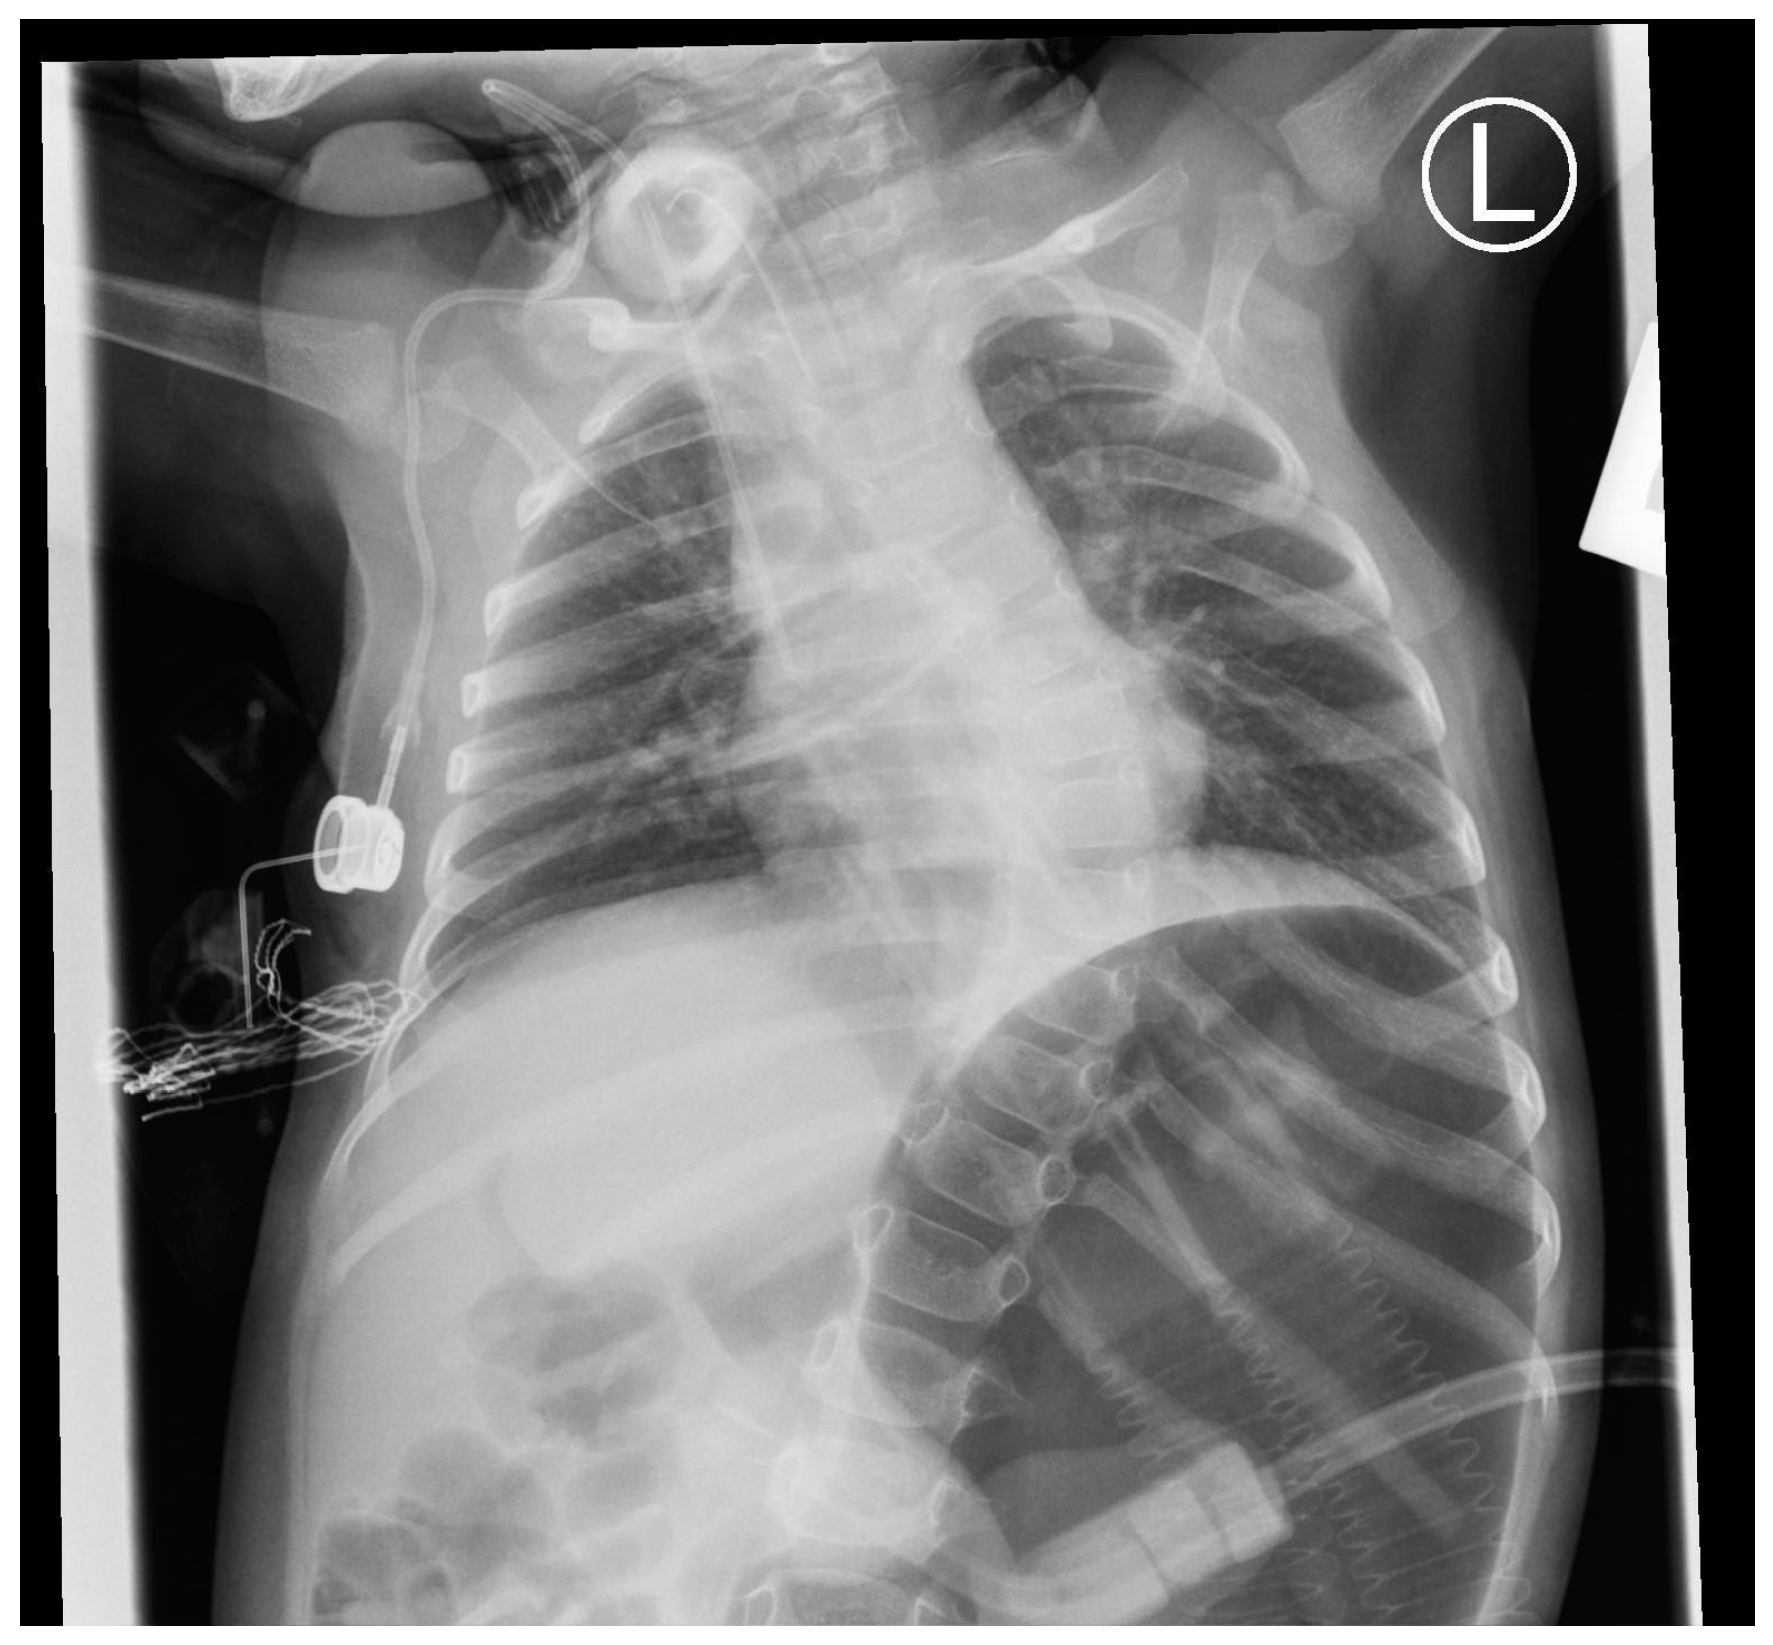

Upon admission to the pediatric department at the age of 4.5 months, the patient presented with a guarded general condition, with tachypnea (up to 60 breaths/minute) and tachycardia (ranging from 140 to 180 beats/minute). She exhibited considerable respiratory effort with a diaphragm contraction, adequate oxygenation, inspiratory chest positioning, grunting, and feeble crying. Parents pointed out their child’s decreased sensitivity to pain. Global hypotonia, particularly noticeable in the head–torso axis, and feet plantarflexion position were evident. A neurological examination revealed tongue fasciculations, a weak sucking reflex, decreased muscle tone in the upper and lower extremities with diminished deep tendon reflexes, and talipes equinovarus. In biochemical tests, no significant abnormalities were found. Echocardiography indicated the possibility of left ventricular hypertrophy. The brain and spinal canal MRI showed no significant abnormalities. No abnormalities in the larynx were detected. Throughout the hospitalization, the patient was fed orally and by gastric tube in a ratio of 30%:70%, achieving satisfactory weight gain (1000 g per month). Initially, due to the episodes of desaturation, passive oxygen therapy was introduced. A chest X-ray showed the eventration of the right hemidiaphragm (Figure 4). The symptoms of respiratory failure were continuously progressing, and at the age of 4.5 months, a tracheostomy was performed. This allowed for the patient to be discharged home for home ventilator therapy.

Figure 4. A chest X-ray of the patient no. 3 with right-sided eventration of the diaphragm at 4 months.